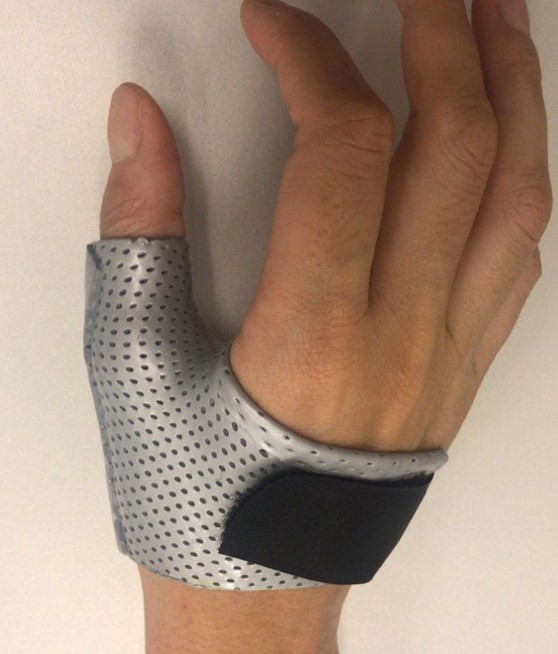

- A custom-made thermoplastic thumb splint is commonly required for approximately 4-6 weeks, depending on injury severity.

Splinting